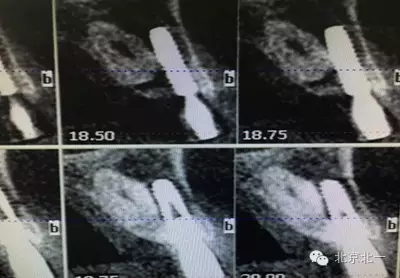

患者種植一月后種植區(qū)不適,偶有疼痛來院拍片發(fā)現(xiàn)23埋伏牙,與種植體相鄰,如圖一、二、三、四所示。

本病例建議:北一種植王明老師建議拔除埋伏牙,并同期植骨,觀察植體情況。提前告知患者失敗等風(fēng)險,簽署同意書。